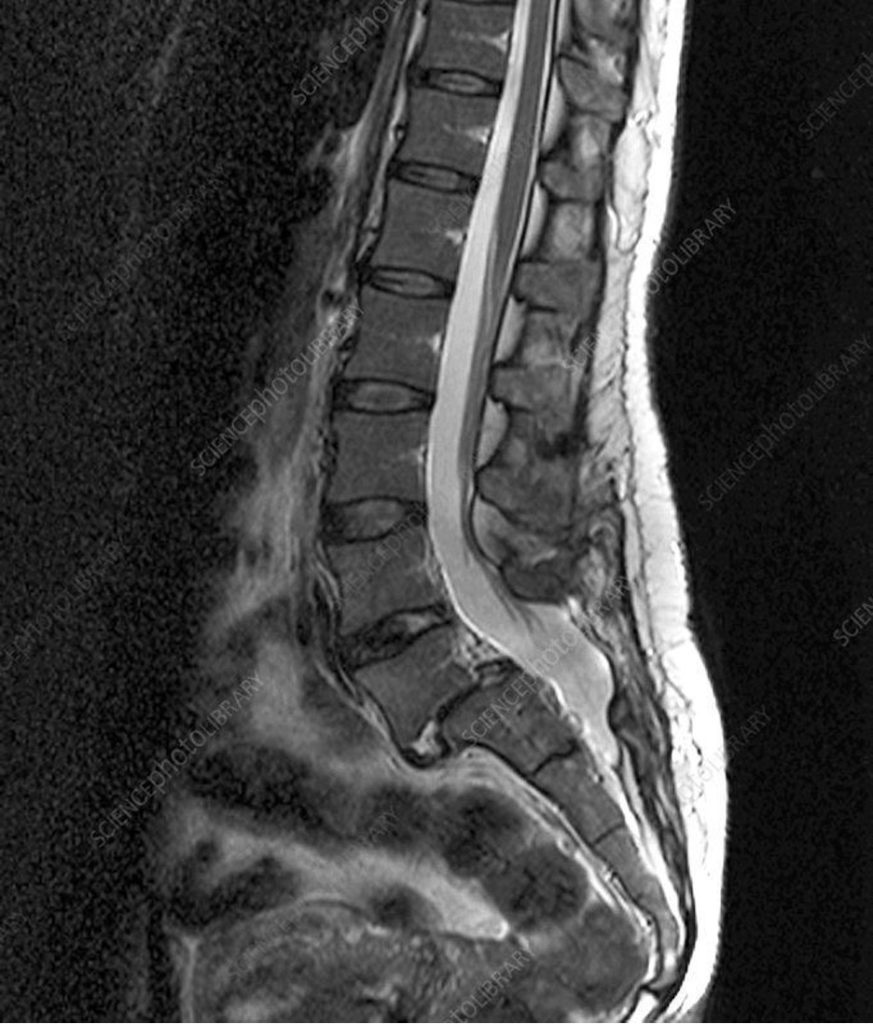

Lumbar spondylolisthesis is usually diagnosed after your neurosurgeon sees you and does a history and physical examination. Your neurosurgeon might then order an MRI of the lumbar spine or CT scan of the lumbar spine. Sometimes a Flexion/Extension Lumbar spine X-ray is also ordered. This is an X-ray that is performed when you bend forward and backwards to see if the spine bones are moving abnormally.